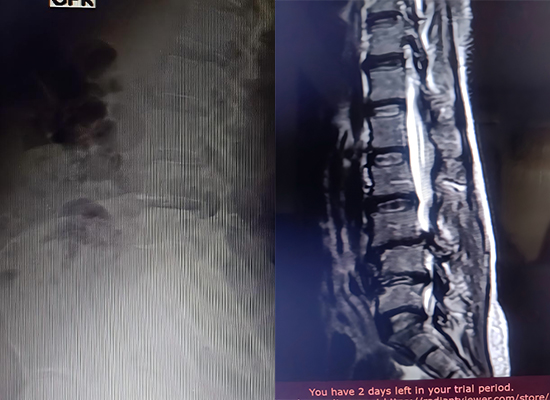

Imágenes posoperatorias que muestran una fijación estable mediante un sistema de tornillos pediculares

Se realizó laminectomía descompresiva L3-L5, seguida de la inserción de la caja TLIF en los niveles L3/4 y L4/5, con fijación con tornillos pediculares.

Fijación estable lograda